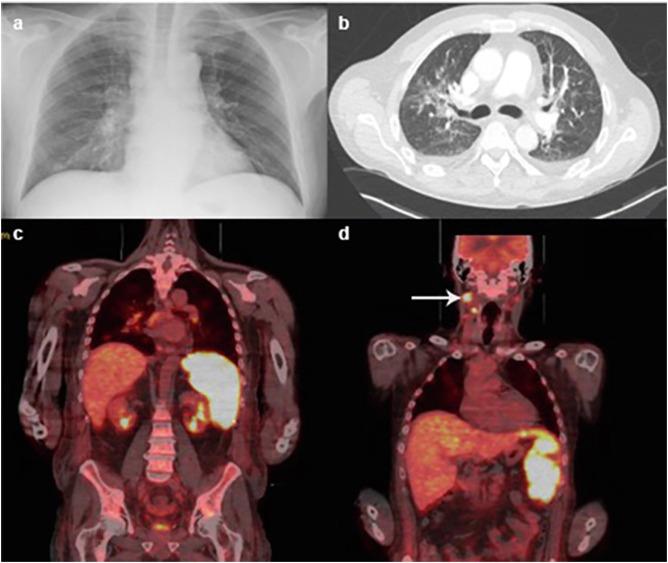

The initial clinical presentation consisted of cough, shortness of breath and fever. Pancytopenia, markedly elevated ferritin and d-dimer were present. Computed tomography (CT) showed bilateral ground glass changes consistent with COVID-19, widespread lymphadenopathy and splenomegaly. A subsequent combined nose and throat swab was positive for severe acute respiratory syndrome coronavirus 2 (SARS-CoV-2). HLH was suspected based upon the H-score and Anakinra, an IL-1 receptor antagonist, was commenced. Liver function acutely worsened and magnetic resonance cholangiopancreatography (MRCP) revealed hepatic haemosiderosis. Intense splenic and cervical lymph node uptake were seen on a positron emission tomography (PET) scan and high doses of intravenous steroids were administered due to concerns over haematological malignancy.

最初的临床表现为咳嗽、呼吸急促和发热。存在全血细胞减少、铁蛋白和D-二聚体显著升高。计算机断层扫描(CT)显示双侧磨玻璃样改变,符合COVID-19表现,伴有广泛的淋巴结肿大和脾肿大。随后的联合鼻拭子和咽拭子检测严重急性呼吸综合征冠状病毒2(SARS-CoV-2)呈阳性。基于H评分怀疑为HLH,并开始使用白细胞介素-1受体拮抗剂阿那白滞素。肝功能急剧恶化,磁共振胰胆管造影(MRCP)显示肝脏含铁血黄素沉着症。正电子发射断层扫描(PET)显示脾脏和颈部淋巴结摄取强烈,由于担心血液系统恶性肿瘤,给予了高剂量静脉类固醇治疗。